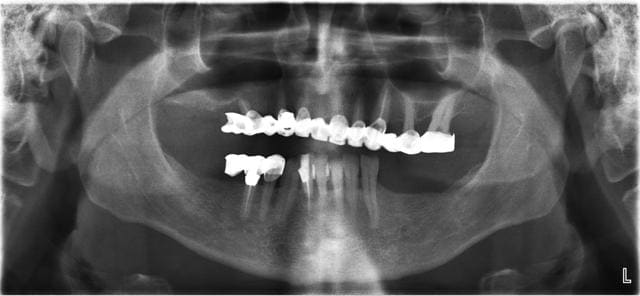

Jeff dans ce cas clinique le plan de traitement a été : empreinte des maxillaires

DVO

Positscan

S.I.A.O

Projet implantaire : extractions, pose de 4 implants, MCI sur 5 implants en récupérant le pilier de l’implant fonctionnel

Validation

Chirurgie

Dans un deuxième temps, les greffes de sinus sont programmées pour la pose de 4 implants

Projet prothétique final : bridge implanto-porté sur 9 implants

Ps : le bridge en pré-op a 15 ans et les implants était bien antérieur.